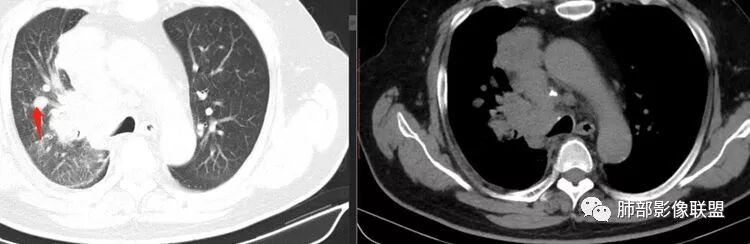

局限性中央间质增厚,考虑癌性淋巴管炎

部分区域有结节感

Coke with ice: 这个是标记的结节感吗?

南边: 奇怪,你们都不觉得这里有结节?

了: 气腔结节

毛勤香: 这个人有癌淋,有点结节感

Coke with ice: 嗯,不明显的结节感可以考虑用MPR和薄层结合起来看,会不会判断的更准一些

2.右肺小叶间隔增厚伴微小结节,提示癌性淋巴管炎。